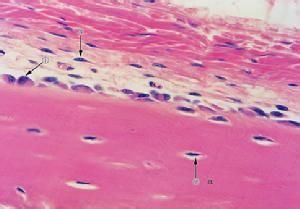

是參與骨組織形成的細胞,排列在骨化部位的表面,不久,其本身被骨基質所包圍,形成骨細胞。